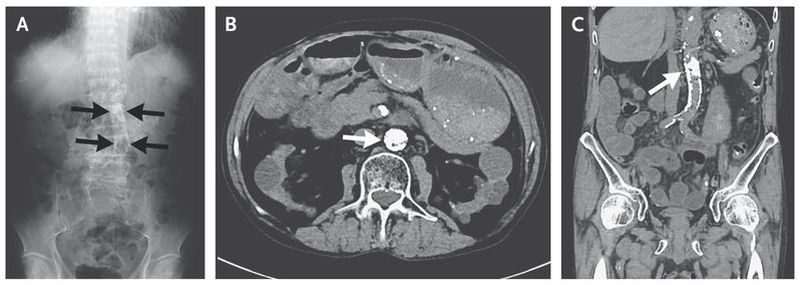

A 62-year-old man presented with a 3-week history of abdominal pain and refractory ileus. He had a 6-year history of continuous ambulatory peritoneal dialysis and a 10-year history of hemodialysis. A radiograph (Panel A) and computed tomographic (CT) scans (Panel B shows the axial view, and Panel C the coronal view) of the abdomen revealed marked calcification (arrows) of the wall of the abdominal aorta, with near-total occlusion and severe stenosis of the superior mesenteric artery. An echocardiogram showed severe aortic-valve stenosis with moderate regurgitation, moderate mitral-valve stenosis with regurgitation, and tricuspid-valve regurgitation. Although the severe stenosis of the aorta and the superior mesenteric artery was considered to be a causative factor in the formation of the ileus, total replacement of the abdominal aorta with bypass of the superior mesenteric artery was considered to be high-risk owing to the patient’s coexisting conditions. Aortic-valve replacement, mitral-valve repair, and tricuspid annuloplasty were performed to augment the cardiac output. After surgery, the ileus and abdominal symptoms subsided, despite the persisting stenosis and calcification of the abdominal aorta.